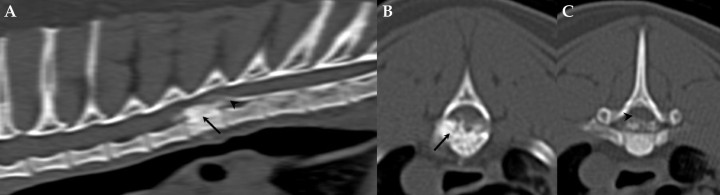

Las radiografías obtenidas de la columna torácica y lumbar demostraron esclerosis y proliferación ósea en la vértebra T6, con posible afección del canal vertebral (incremento de radiodensidad a nivel de T6) (Fig. 1). Seguidamente se procedió a la realización de una resonancia magnética (RM) de la columna torácica y lumbar en la que se evidenció una lesión que ocupaba el espacio epidural, hipointensa en secuencias T2W e isointensa en secuencias T1W en relación con la sustancia gris medular. Esta lesión manifestaba mínimo realce tras la administración de contraste endovenoso y se originaba a partir del cuerpo vertebral de T6, del que se diferenciaba difícilmente, ocupando el aspecto ventrolateral izquierdo del canal vertebral y produciendo una compresión severa del cordón medular (Fig. 2). Dada la escasa resolución y detalle de las alteraciones óseas se procedió a la realización de una tomografia computarizada (TC) tras la administración de contraste intratecal (mielo-TC) en la que se observaron extensos fenómenos osteoproliferativos centrados en el cuerpo y pedículo izquierdo de T6 que invadían el aspecto ventrolateral izquierdo del canal vertebral induciendo una desviación severa del cordón medular (Fig. 3). La lesión producía un patrón compresivo extradural con atenuación del anillo de contraste. No se evidenciaron signos de reacción perióstica pero sí pequeñas áreas puntiformes radiolúcidas en el hueso neoformado (Fig. 3B). Previamente a la inyección de contraste intratecal se obtuvo una muestra de líquido cefalorraquídeo que no reveló alteraciones ni en el recuento ni en el tipo celular. El diagnóstico radiológico fue el de una lesión ósea focal que ocupaba el espacio epidural, originada a partir del cuerpo de T6 con compromiso medular severo cuyos diagnósticos diferenciales incluyeron osteomielitis, granuloma inflamatorio, neoplasia ósea, neoformación ósea como consecuencia de traumatismo previo o malformación vascular ósea.

<p>(<strong>A</strong>) Reconstrucción sagital de la columna torácica. (<strong>B</strong>) Imagen transversal a nivel del cuerpo vertebral de T6 obtenida mediante mielo-TC. (<strong>C</strong>) Imagen transversal a nivel del borde caudal del cuerpo vertebral de T6 obtenida mediante mielo-TC. Se aprecia engrosamiento del cuerpo y pedículo izquierdo de T6 con compromiso del canal vertebral por la lesión epidural hiperatenuante de bordes bien definidos y áreas de hipoatenuación que le confieren un aspecto granulado (flechas en <strong>A</strong> y <strong>B</strong>). Nótese la deformación del cordón medular característica de una lesión epidural (puntas de flechas en <strong>A</strong> y <strong>C</strong>).</p>

Figura 3

(A) Reconstrucción sagital de la columna torácica. (B) Imagen transversal a nivel del cuerpo vertebral de T6 obtenida mediante mielo-TC. (C) Imagen transversal a nivel del borde caudal del cuerpo vertebral de T6 obtenida mediante mielo-TC. Se aprecia engrosamiento del cuerpo y pedículo izquierdo de T6 con compromiso del canal vertebral por la lesión epidural hiperatenuante de bordes bien definidos y áreas de hipoatenuación que le confieren un aspecto granulado (flechas en A y B). Nótese la deformación del cordón medular característica de una lesión epidural (puntas de flechas en A y C).